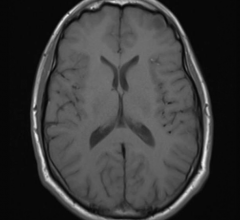

Patients with the most common form of focal epilepsy have widespread, abnormal connections in their brains that could provide clues toward diagnosis and treatment, according to a new study published online in the journal Radiology.

For the first time, researchers have confirmed an association between a common magnetic resonance imaging (MRI) contrast agent and abnormalities on brain MRI, according to a new study published online in the journal Radiology. The new study raises the possibility that a toxic component of the contrast agent may remain in the body long after administration.